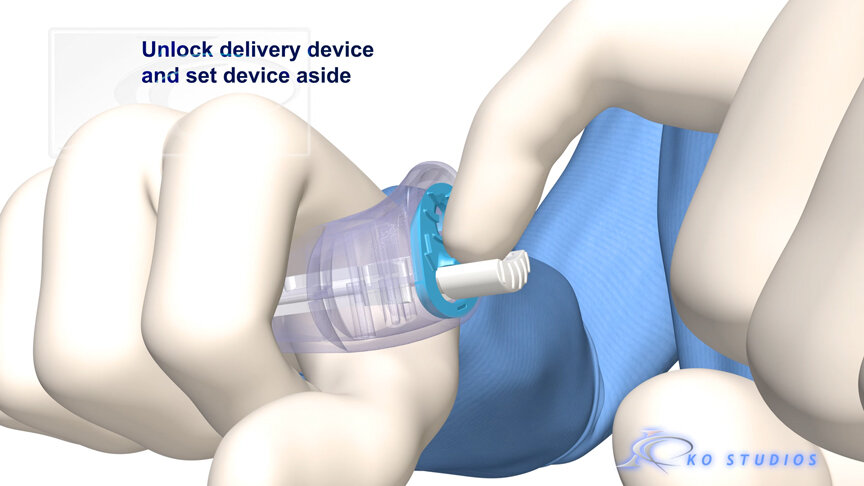

EnCompass F2 Device for cerebral embolic protection system in TAVR procedures

EnCompass Technologies

EnCompass’ F2 filter has pores small enough to block most emboli to the brain while preserving blood flow. During the TAVR procedure, 360-degree wall apposition of the filter in the aortic arch prevents migration. The filter, attached to a self-expanding, nitinol stent, is easy to insert, deploy and retrieve, according to the company. Copyright ©2021 KO Studios.